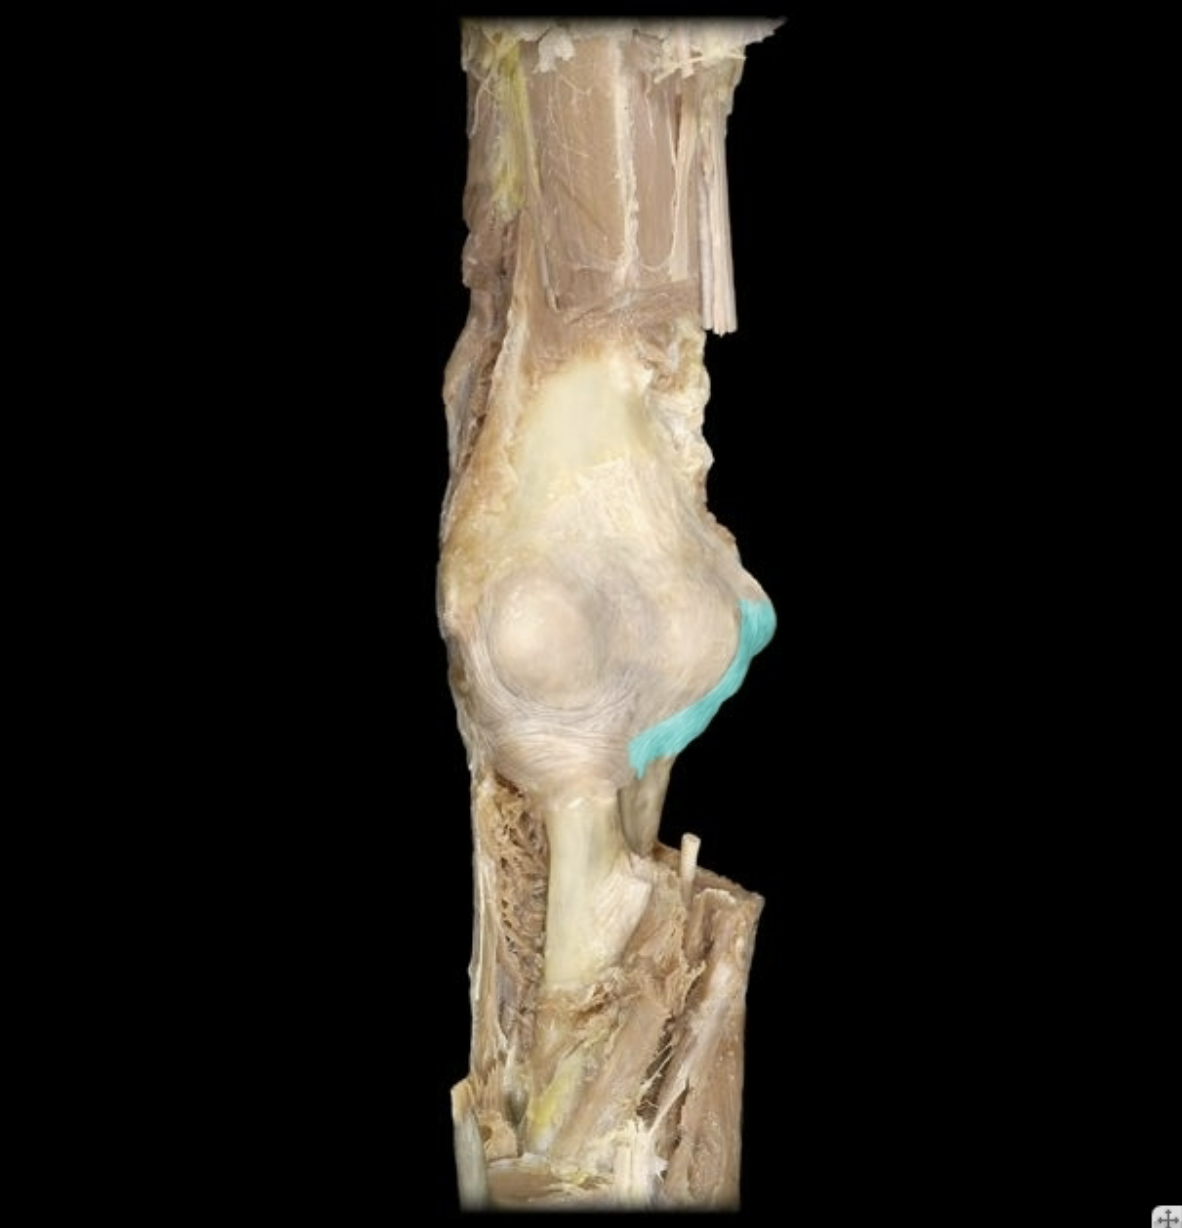

Lateral collateral ligament

Lateral meniscus